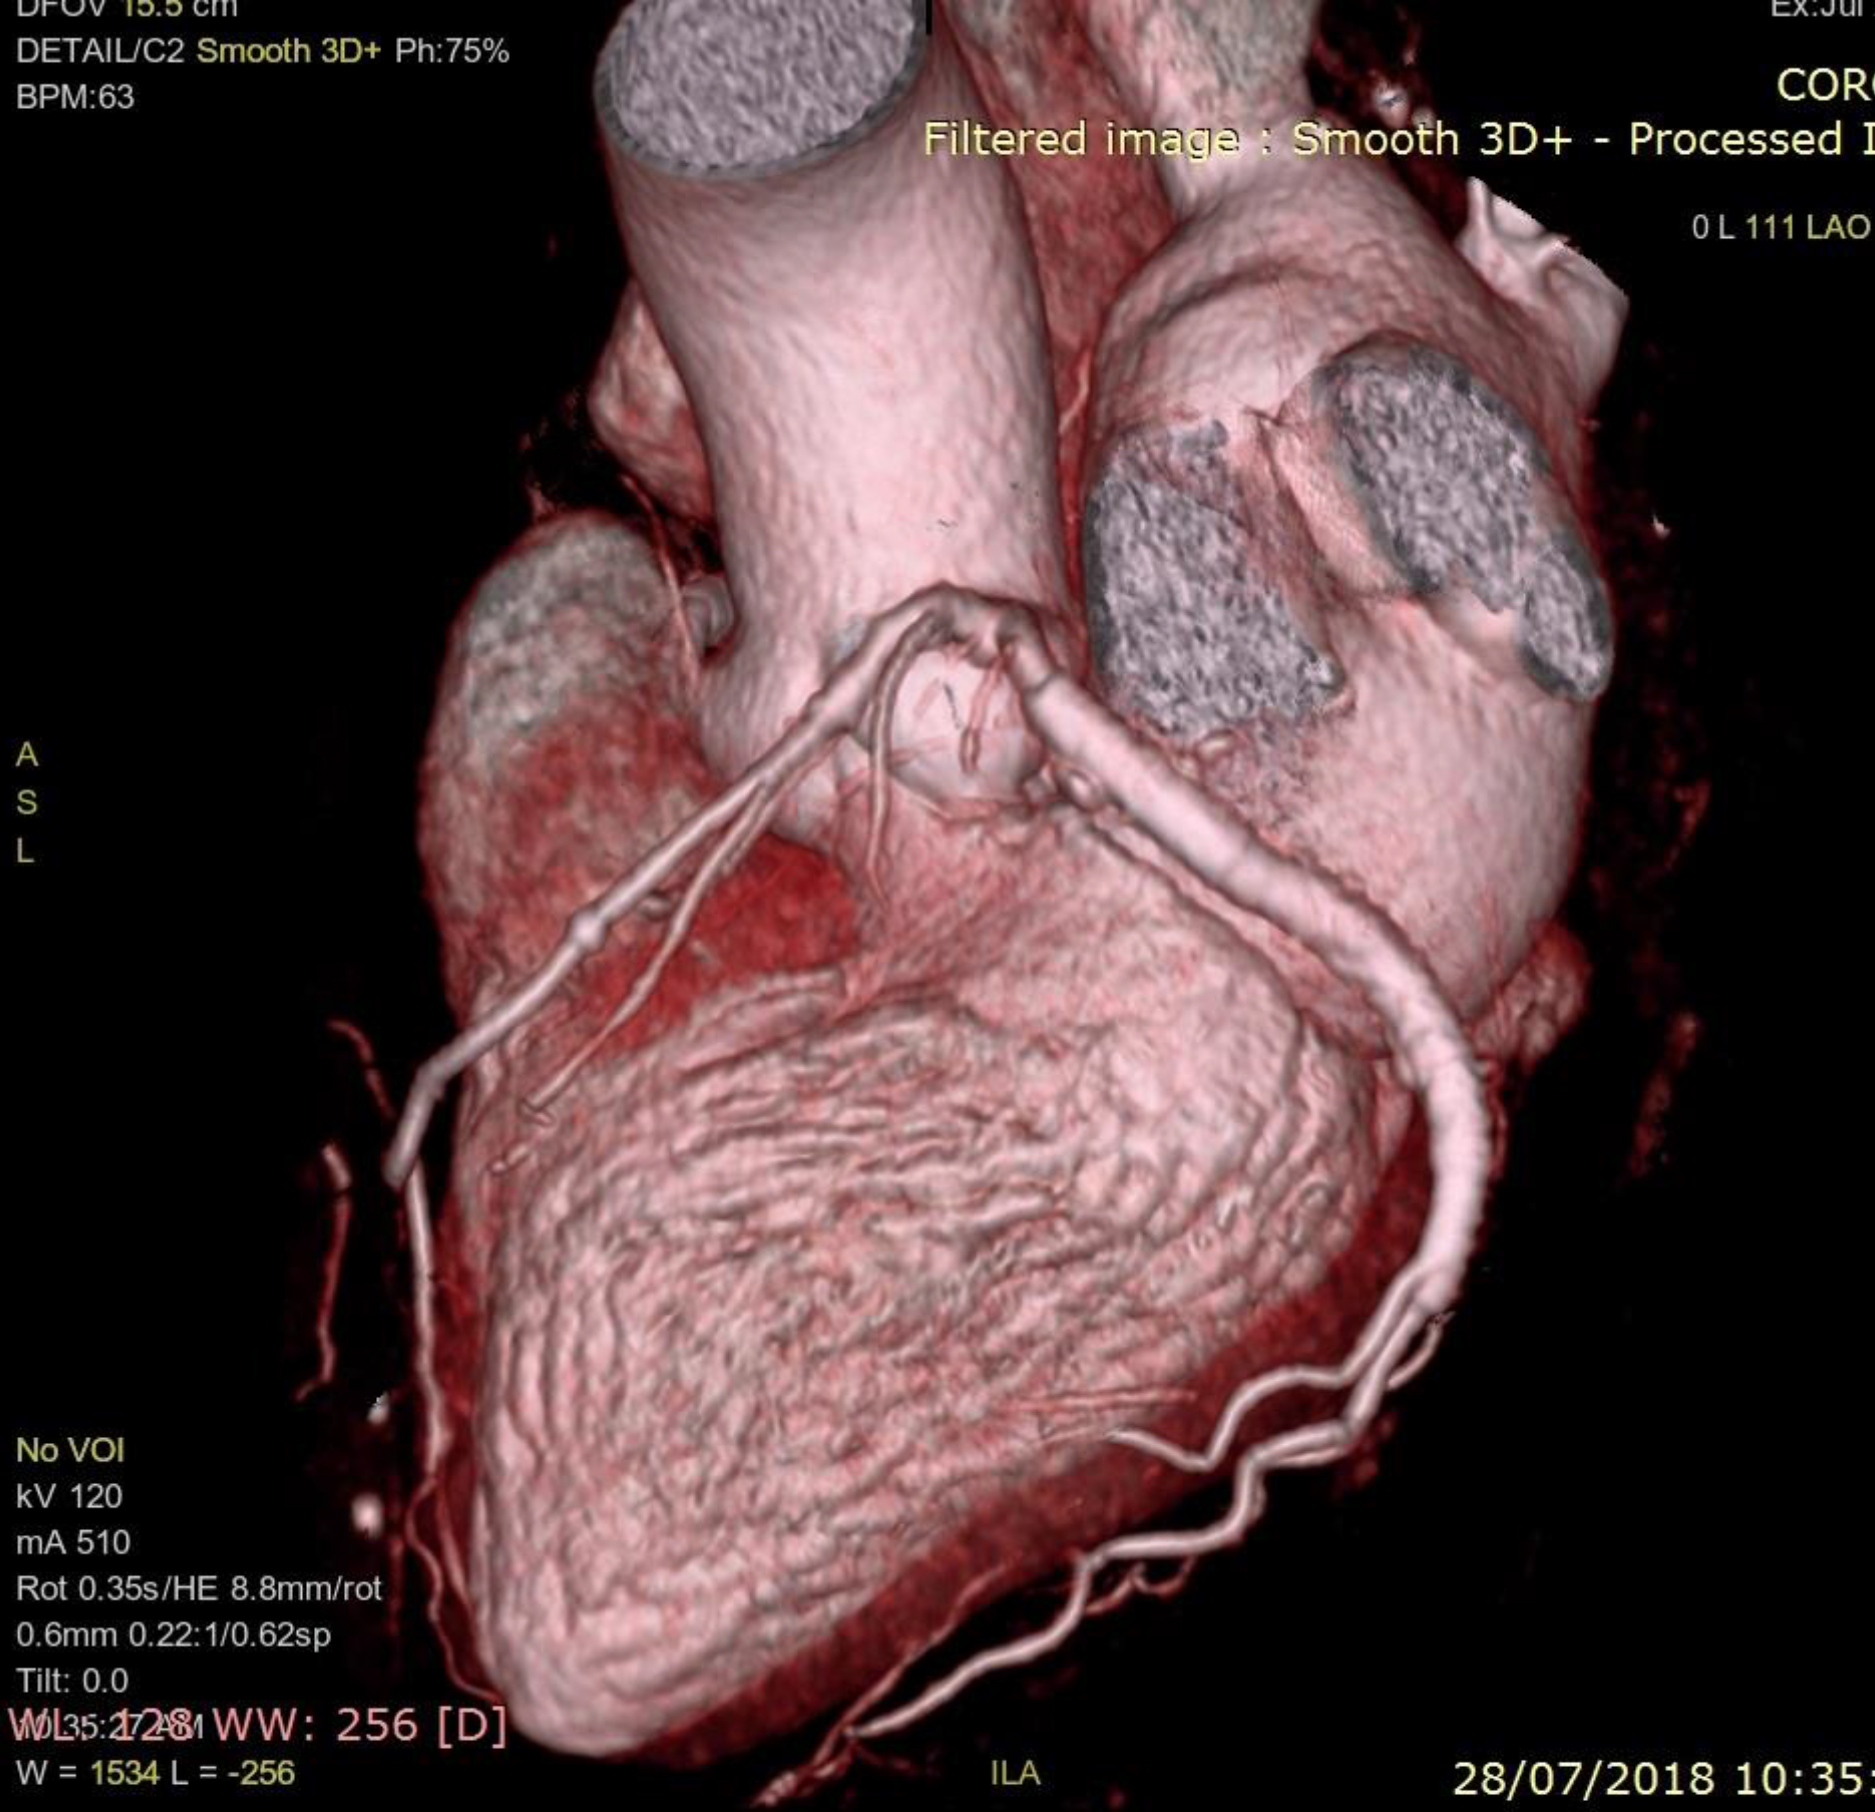

The patient was discharged on dual antiplatelet and high dose statins (Ticagrelor 90mg bd and Aspirin 75 mg OD, Atorvastatin 80 mg OD). CT coronary angiography at follow up showed no leak into the aneurysm, the aneurysm was thrombosed (Figure 5). She was asymptomatic and was advised the same medication to continue.

Figure 5: Three dimensional volume rendered computed tomography image of the heart showing the absence of the pseudoaneurysm and patent stent in the left circumflex artery.